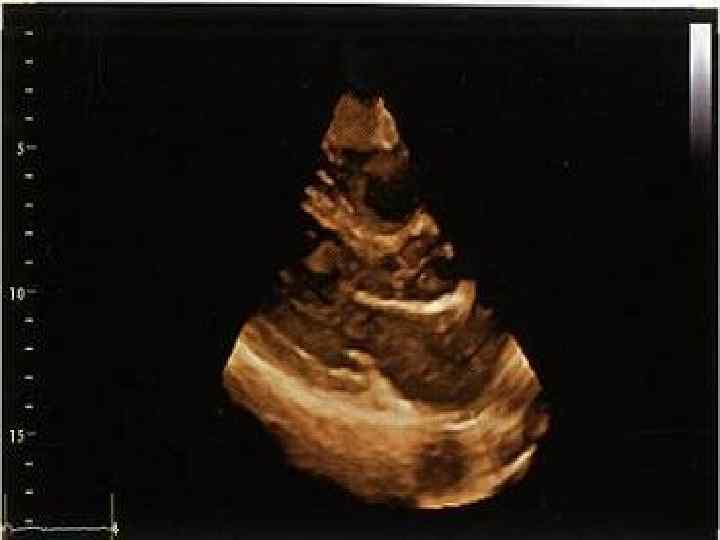

Виды эхокардиографии • Трансторакальная ЭХО КГ • Чреспищеводная ЭХО КГ • Стресс ЭХО КГ • Контрастная ЭХО КГ • Интраоперационная ЭХО КГ • Внутрисосудистая ЭХО КГ